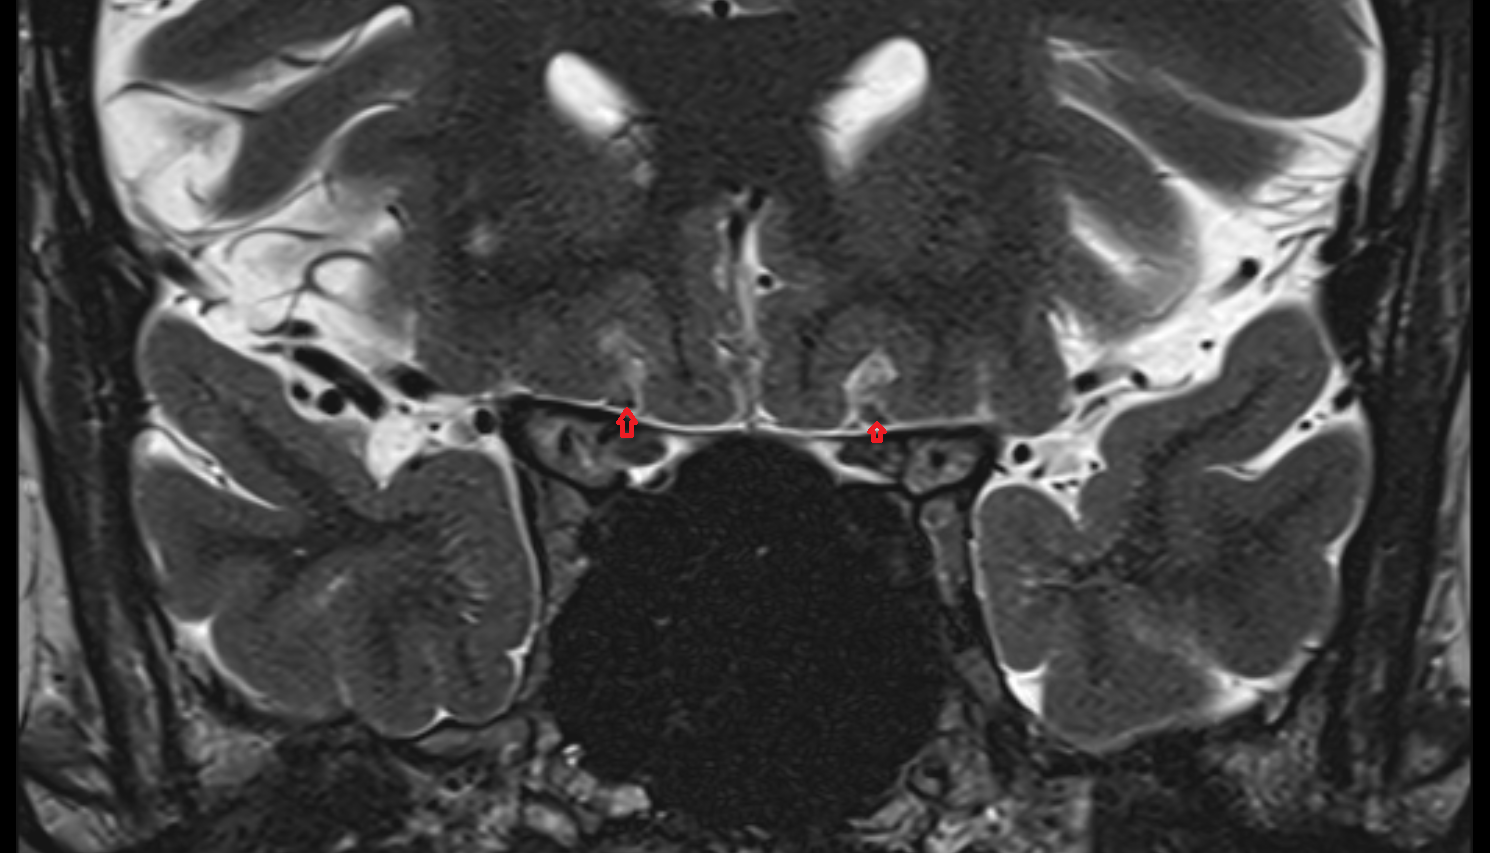

- Peripheral zone of prostate

- Anterior Fibromuscular Stroma of prostate

- Central zone of prostate

- Transitional zone of prostate